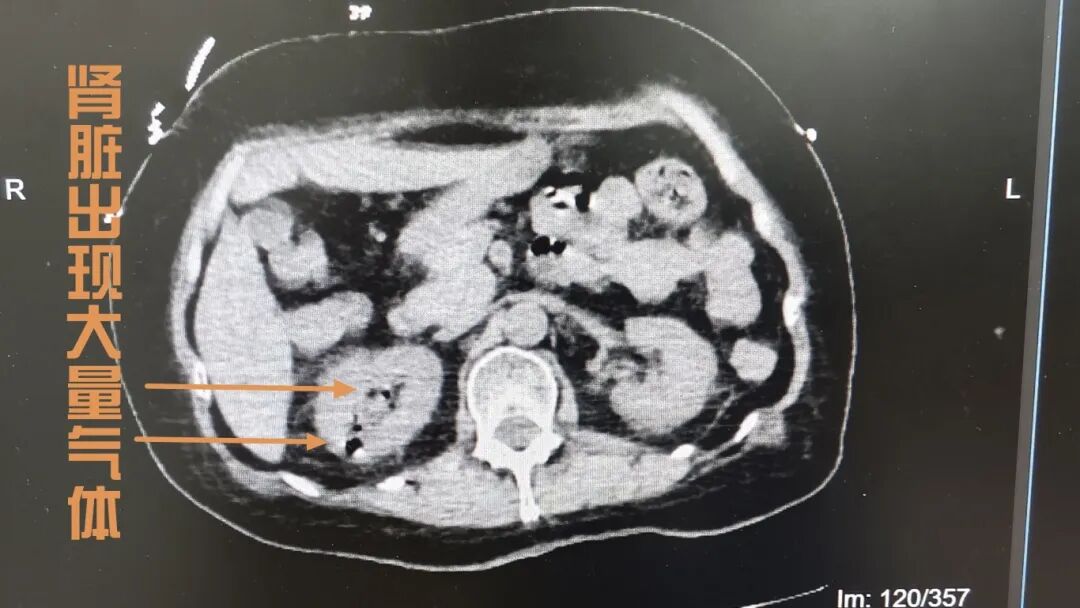

随后,患者被紧急转入综合内科。补液、纠正酮症、抗感染、升压……医护团队有条不紊地实施抢救,全力稳定生命体征。但致命的“元凶”仍未找到,为明确病因,医生立即为患者完善腹部CT检查,结果让所有医护都高度警惕:患者右侧肾脏、输尿管及膀胱内,遍布大量气体!这是气肿性肾盂肾炎——一种由产气致病菌引发、病死率极高的泌尿系统重症感染。